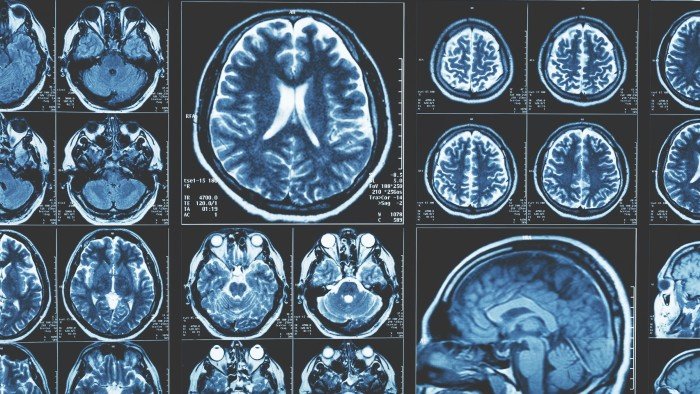

La rapidez con la edad del cerebro de un individuo es, con mucho, el factor más importante que determina la longevidad, los científicos han concluido, después de estudiar el envejecimiento de 11 órganos y tejidos diferentes en el cuerpo humano.

Investigadores de la Universidad de Stanford en California analizaron proteínas extraídas de 45,000 muestras de sangre de personas. Trazaron las proteínas a su órgano de origen para calcular su «edad biológica», una medida de desgaste, que puede diferir de su «edad cronológica».

La edad biológica del cerebro juega un papel mucho más importante en la determinación de la vida útil que la edad biológica del músculo, el corazón, el pulmón, las arterias, el hígado, los riñones, el páncreas, el sistema inmune, el intestino y la grasa, encontraron.